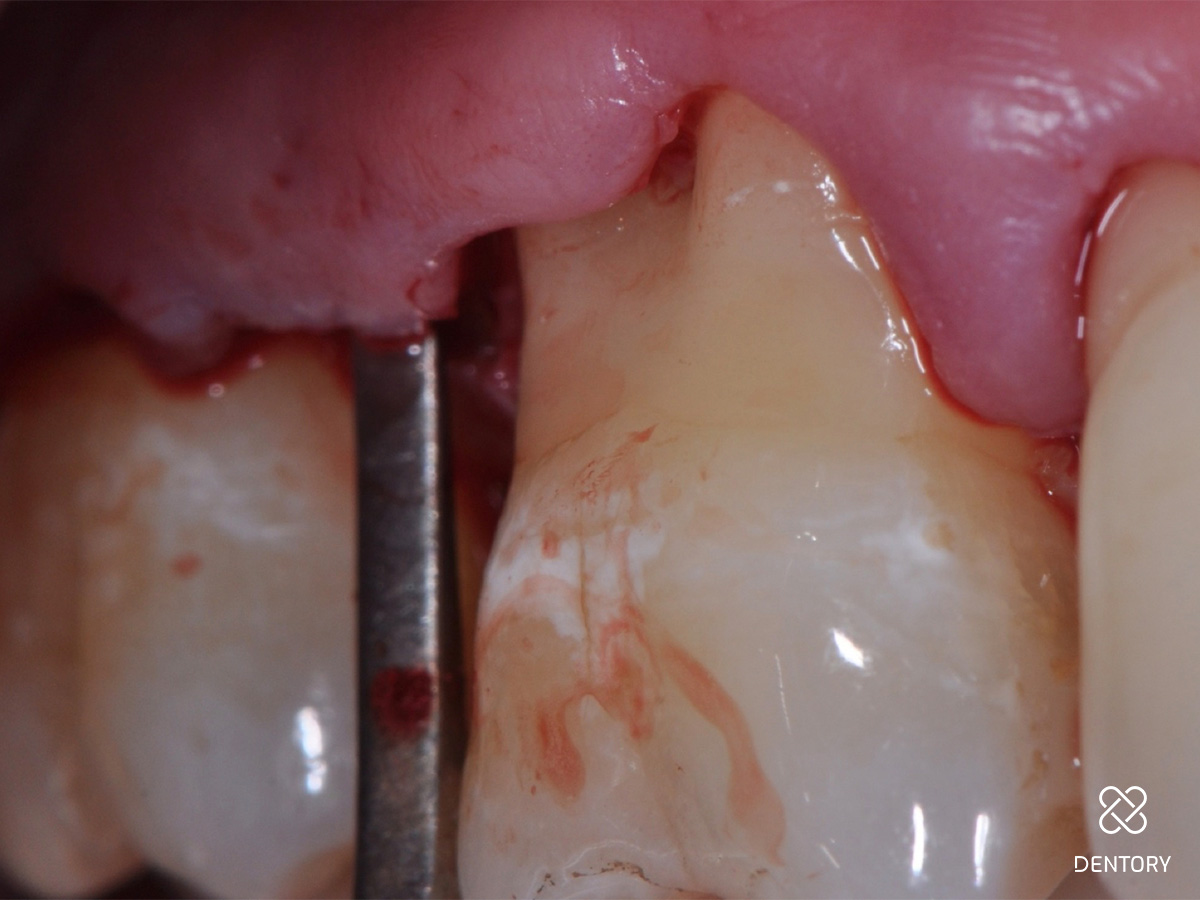

Abbildung 2

Die Ausgangssituation der regio 16/17. Hier wurden initial Sondierungstiefen von 9 und 11 mm mesial an Zahn 17 gemessen.